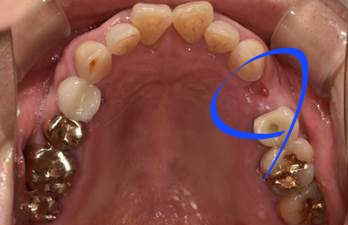

(후) 2022-01-11

이분은 SCRP 방식이라고 해서 보철물 분리가 가능한 타입으로 진행해 드렸는데요.

자세히 보시면 크라운 중앙에 구멍이 뚫려있는 것이 보이실 것입니다.

나중에 보수가 필요할 때 레진만 제거한 후 헐거워진 나사를 조이거나 풀 수 있고, 청소한 후 다시 씌우 수 있다는 장점이 있습니다.

한번 붙인 보철물도 언제든지 수정이 가능하다는 점 때문에 장기적으로 유지관리 측면에서 장점이 많은 방식입니다.